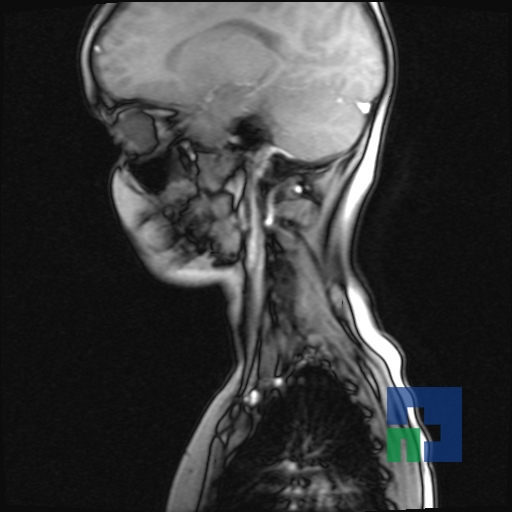

Examinare de rutină cerebrală, nativ și cu substanță de contrast (SDC) pentru diagnosticul:

- Accidentelor vasculare cerebrale ischemice sau hemoragice

- Evaluarea deplasării liniei mediane

- Evaluarea cisternelor perimezencefalice

- Diagnosticul edemului cerebral, a contuziei cerebrale, a leziunilor axonale difuze edematoase/hemoragice, a dilacerării cerebrale, a hematomului intraparenchimatos posttraumatic, a hematoamelor subdurale/extradurale (acute, subacute, cronice), a hemoragiei intraventriculare, a hemoragiei subarahnoidiene